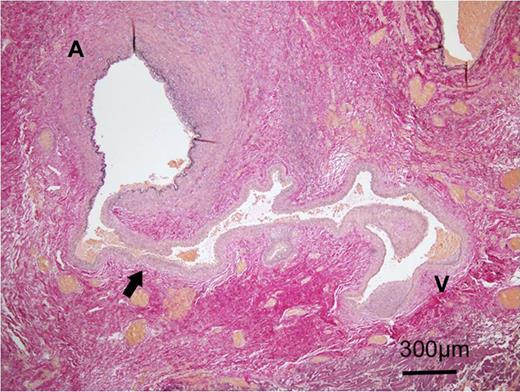

A 24-year-old male was admitted to our hospital after a traffic accident. Computed tomography scan had shown an acute epidural hematoma on the right surface of frontal lobe, which was emergently treated by surgical evacuation. One month later, he began to complain of pulsatile tinnitus in the left ear. A head magnetic resonance angiogram showed an extremely dilated vein in the left temporal region (Fig. 1). An angiography revealed a direct shunt between the left parietal branch of the STA and the superficial temporal vein (STV) in the preauricular region as well as an aneurysm in the left frontal branch of the STA (Fig. 2). He underwent surgery to remove the AVF and the aneurysm (Fig. 3). Pulsatile tinnitus disappeared immediately after surgery. Histopathological examination demonstrated that the artery was connected to the vein through the thin-walled vessels lacking internal elastic lamina and muscularized media, suggesting that the connecting vessels were newly formed (Fig. 4).

Histopathological photomicrograph with Elastica van Gieson stain showed that a thin-walled vessel lacking in internal elastic membrane (arrow) connected the artery (A) and the vein (V).